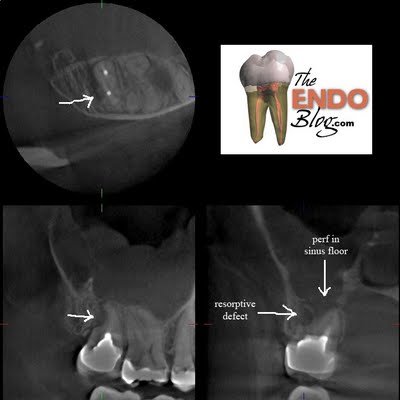

Radiographs reveal peripical radiolucency and conical shaped root. Two canals have been filled. My assumption is that this is likely a c-shaped canal that was incompletely treated. We decided to take a CBCT to evaluate the root form to determine if there is a missed canal or c-shaped canal. If a canal is missed, then retreatment will be recommended. If all the canals were found, then we might consider a surgical approach.

I was surprised to see a large resorptive defect on the DB root surface. This defect has destroyed most of what was once a DB root. Non-surgical retreatment of this tooth would result in perforation and extrusion of RCT material, and likely failure. It was determined that surgical treatment of this tooth would also have a poor prognosis as well. Extraction has been recommended.

Also noted was a perforation in the floor of the Mx sinus, with adjacent sinus inflammation. This tooth is also causing a sinusitis of dental origin. Removal of this tooth should help clear up some of the chronic sinus issues the patient has been experiencing.